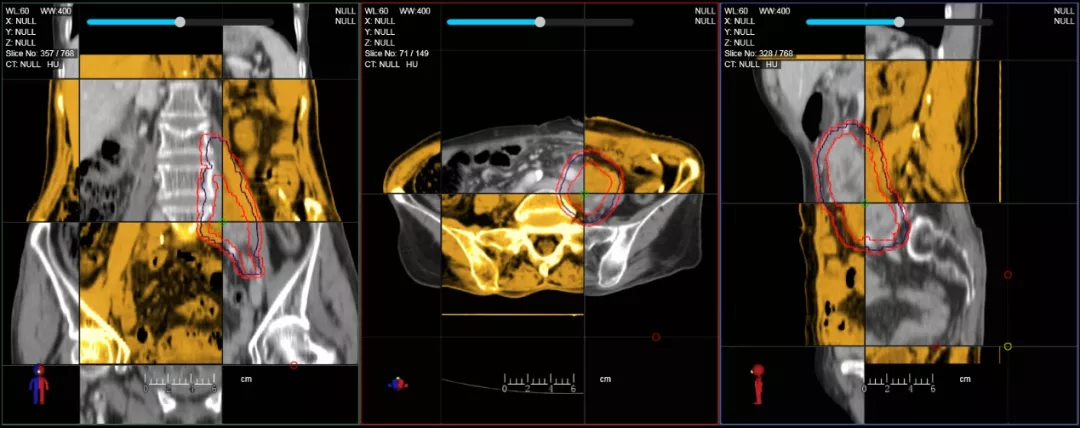

在線自適應(yīng)放療流程示意圖